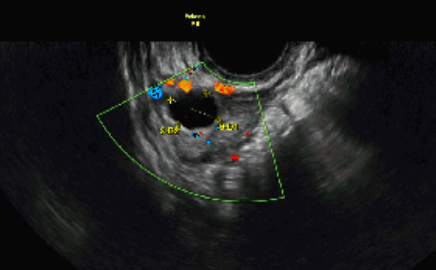

Antral follicle count (AFC) is measured using a transvaginal ultrasound — a type of scan that offers a close-up look at your ovaries. This is usually done before ovulation, when the small resting follicles (called antral follicles) are most visible, but can be done at any time in your cycle. Each follicle appears as a tiny black bubble on the screen, and the clinician will count how many they can see in each ovary. [3]

Image of an antral follicle count ultrasound — an ovary showing 3 follicles (highlighted in red and yellow).

Source: Tassia O’Callaghan